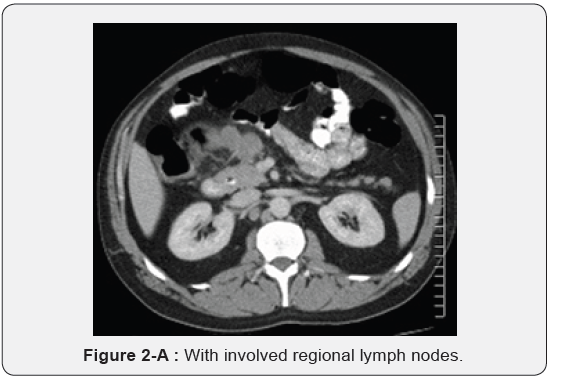

Immunohistochemistry revealed a strong positivity for AE1/ AE3 and Cytokeratin 20 (CK20), and PASD stained for mucin, but the staining for Cytokeratin 7 (CK7), p63, and TTF-1 was negative. The findings suggested a likely primary colorectal origin. He underwent an urgent OGD and full colonoscopy. OGD revealed a normal esophageal mucosa and mild gastritis which tested negative for H. pylori. Full colonoscopy detected a partially-obstructing circumferential mass at the proximal transverse colon near the hepatic flexure. The biopsy report from this colonic mass confirmed an invasive poorly-differentiated colonic adenocarcinoma and the findings were almost identical to the left supraclavicular node’s biopsy. The patient had a computed tomography (CT) scan of the chest, abdomen and pelvis which depicted a locally advanced proximal transverse colon tumor spreading well beyond the serosa posteriorly with local infiltration of pericolic fat and regional lymphadenopathy Figure 2-A. There was a significant metastasis in the para-aortic nodes Figure 2-B, anterior mediastinal nodes Figure 2-C and left supraclavicular nodes Figure 2-D. No evidence of hepatic, pulmonary or bony metastasis noted. Carcinoembryonic antigen (CEA) level was above the normal (22 ng/ml, normal reference <3.5 ng/ml). Alpha-fetoprotein (AFP) level was within the normal ranges.